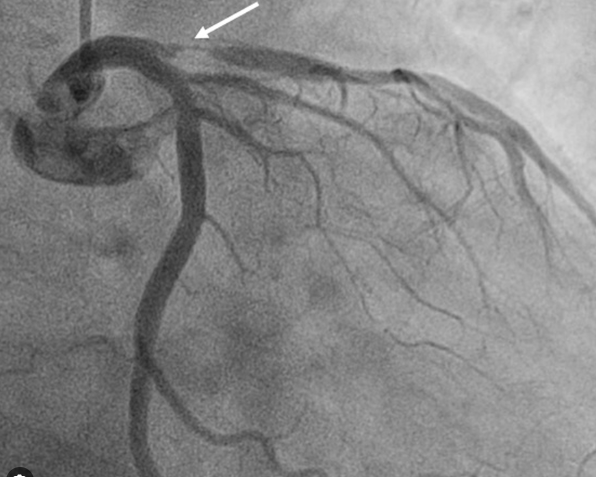

Here is a middle-aged man who went for an annual health check and ended up with this TMT. His exercise capacity was good at 11 METs, stopped at early stage 4 standard Bruce. He was asymptomatic, and every other parameter was normal.

Images: Resting, Peak, severe positive response, in lead V5 and V6. Every cardiologist advised some form of CAG. Opinions were so diverse, ranging between silent left main, tight proximal LAD to innocuous false positive.

What is your inference ? The patient seeked by advice It was indeed an academic stress test. There is a frightening ST depression I said. yes the rest is very likely to be false positive but I don’t have the courage to commit so. Mostly, you can’t escape from a coronary angiogram” . Next option is CT angiogram, Thallium or dobutamine stress.

It was indeed an academic stress test. There is a frightening ST depression . Very difficult to Ignore. May be, it could be false positive but I don’t have the courage to commit so. Mostly, you can’t escape from a coronary angiogram” .Other options are  CT angiogram, Thallium or dobutamine stress.

He smiled and said, “You are absolutely right, doctor. Out of 5 cardiologists I consulted, 4 asked me to go for an immediate angiogram. Still, I escaped because of one Egyptian cardiologist.”

I was eager to see what he did . This is the test he did.

Yes. It was indeed a smart move. The shrewd cardiologist did a bicycle ergometry and simultaneous echocardiogram without any drugs or injections. He could confidently rule out significant CAD (by absence of any wall motion defect). Hats off to him. Lets earn some courage from such truely learnt cardiologist.